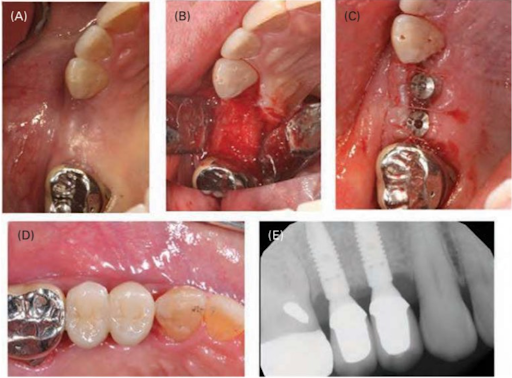

(A) Bốn tháng sau phẫu thuật GBR. (B) Đủ xương chiều ngang tại thời điểm đặt implant. Implant được đặt (C) và làm phục hình (D). (E) Phim quanh chóp của implant đã làm phục hình. Sau 4 tháng lành thương, xương phía ngoài đã tăng lên đáng kể, và 2 implant (đường kính 3.5 mm x chiều cao 11mm) được đặt (theo hướng dẫn của nhà sản xuất) mà không cần phải ghép thêm. Hai tháng sau cấy ghép, tiến hành làm phục hình trên implant.